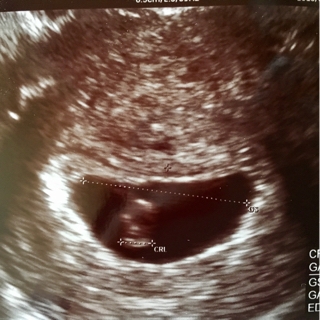

胎嚢25.7mm

胎児4.9mm

5回目

エコー写真は貰えませんでした

子宮の中が、キレイになってエコーには何も写ってなかった

胎嚢 21.4mm

内診、胎嚢の大きさのの割に中に見えるものはなし

胎嚢21.3mm

あれ胎嚢、小さくなってる…

”あれっ、ここに卵黄嚢が見えるね”と

んっ??確かになんか見える?